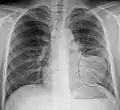

A black and white X-ray picture showing a triangle white area on the left side. A circle highlights the area.

A chest X-ray showing a very prominent wedge-shape bacterial pneumonia in the right lung